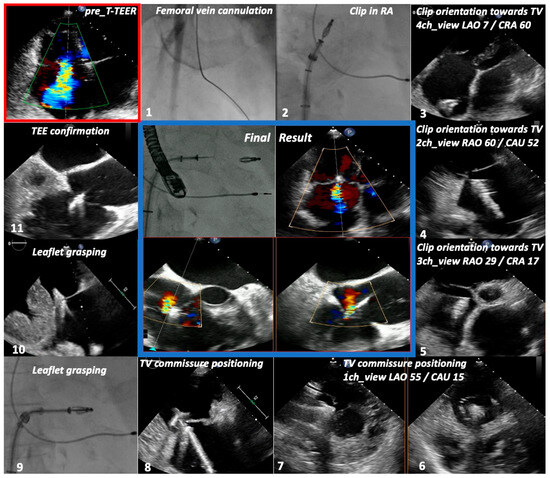

| TTE View | Focus | ||

|---|---|---|---|

| Functional Parameters | Right Heart Morphology | TV Anatomy | |

| PLA standard | LVOT diameter (Qs/CO calculation) | RV function and size (eyeballing) | -- |

| PLA RV inflow RH two-chamber view | TR severity (eyeballing) TR Jet VC and PISA (optional) | RV function and size (eyeballing) | AL visualization SL vs. PL distinction |

| PSA standard RH three-chamber view | TR severity (eyeballing) RVOT VTI RVOT diameter | RV size PA size | Leaflet distinction, if possible |

| PSA-modified alternative RH one-chamber view | TR severity (eyeballing) | TV annulus size Coaptation gap | Simultaneous visualization of all leaflets |

| A4C RH four-chamber view | TR Jet area, VC and PISA TR VTI, RVSP TAPSE RV free wall TDI RV FAC RA volume RV diameters LVOT VTI (A5C/A3C) | RV function and size RA size TV annulus size Tenting height | SL visualization AL vs. PL distinction |

| A2C right alternative RH two-chamber view | TR Jet area, VC and PISA | RA size TV annulus size | AL visualization |

| Subcostal long axis | Hepatic systolic vein flow reversal Inferior vena cava size | RV function and size (eyeballing) | PL visualization AL vs. SL distinction |

| Subcostal short axis RH one-chamber view | TR severity (eyeballing) | Coaptation gap | Simultaneous visualization of all leaflets |